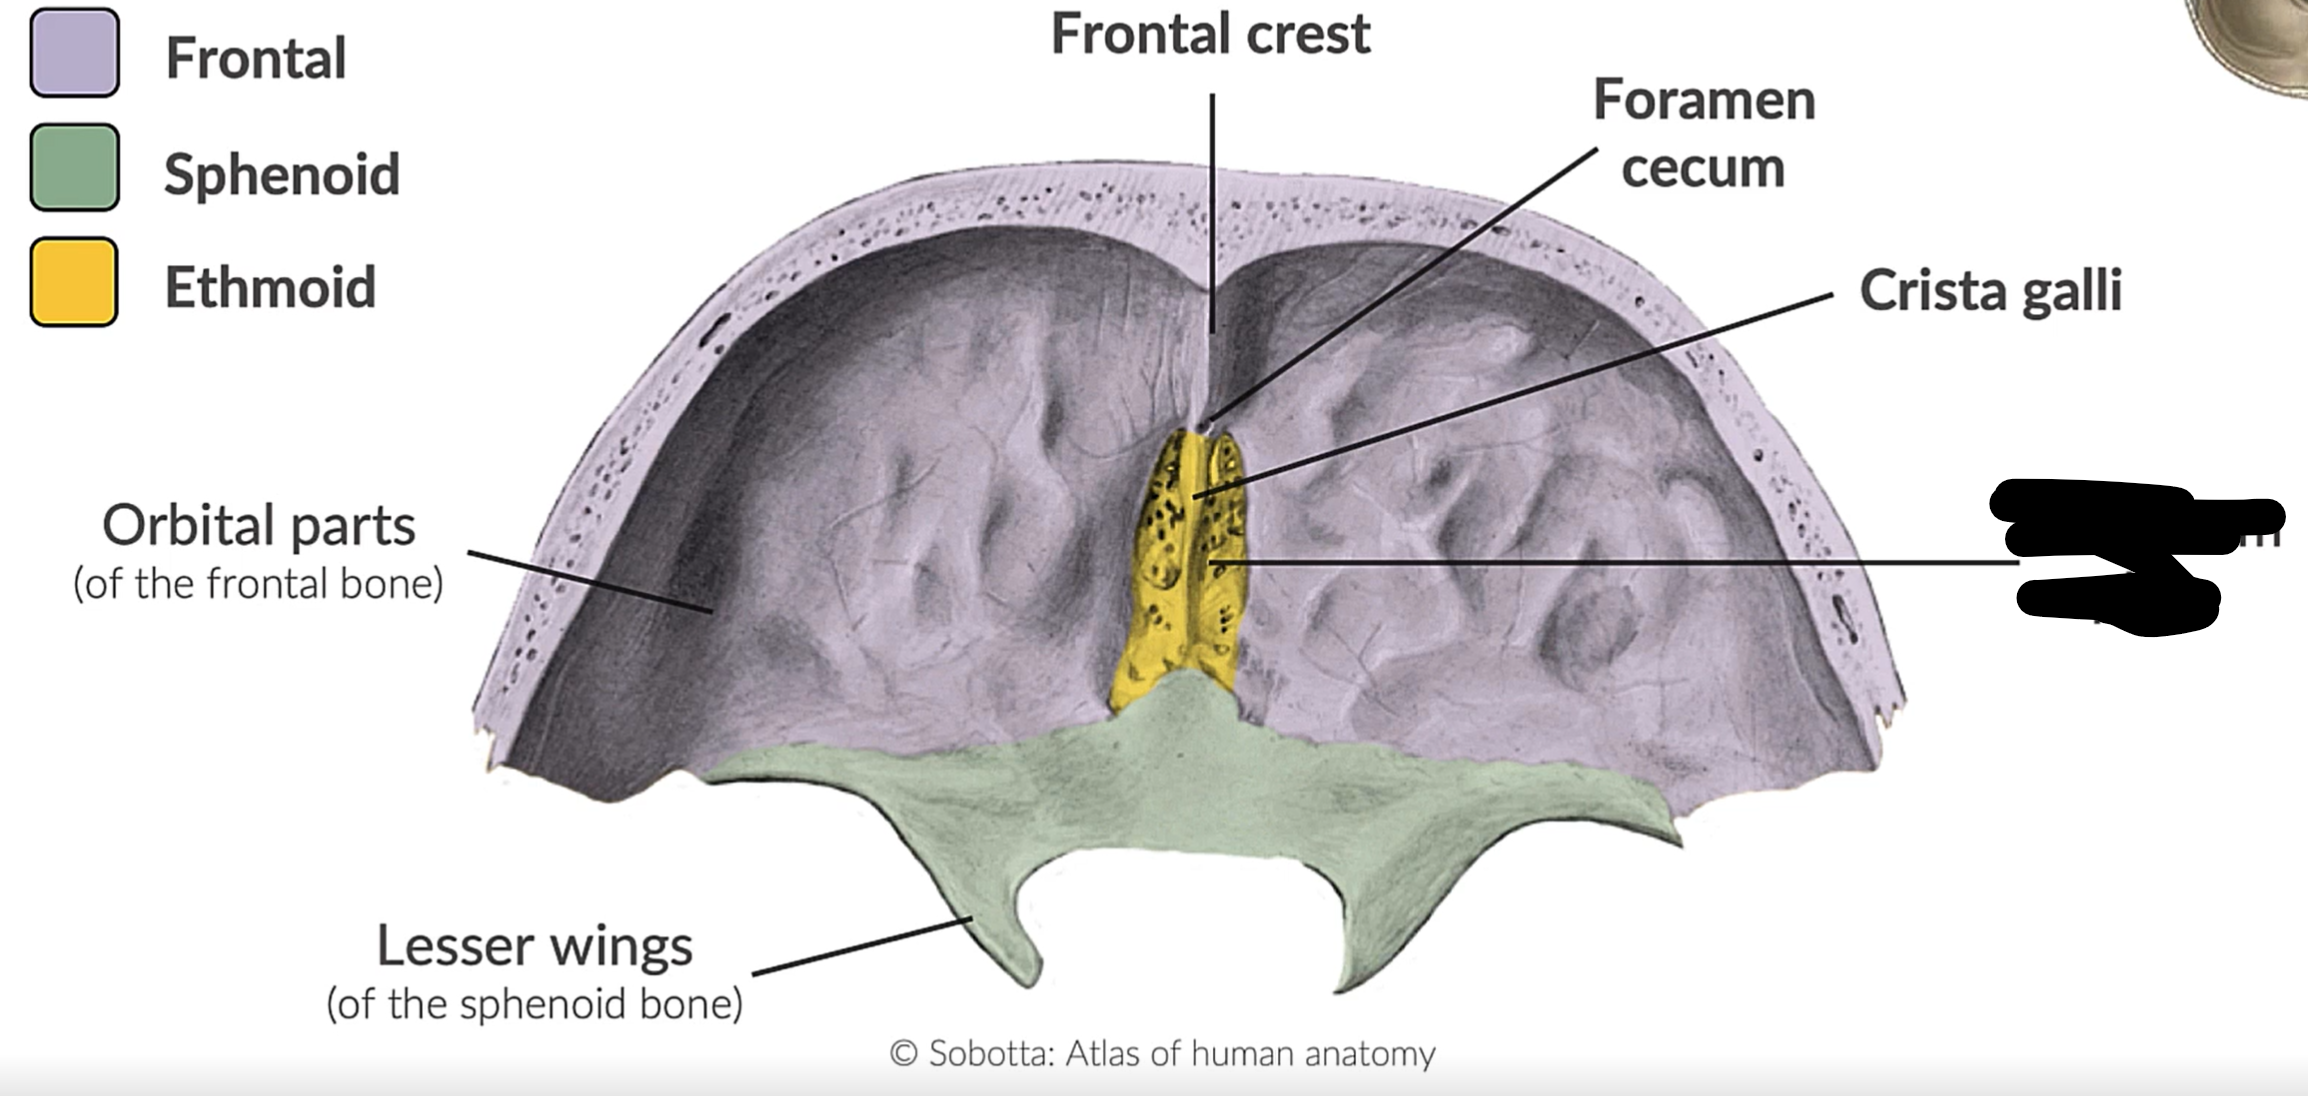

What bones form the anterior cranial fossa?

Frontal, ethmoid and sphenoid

What is this?

Anterior cranial fossa

NN

Crista galli

Foramen caecum